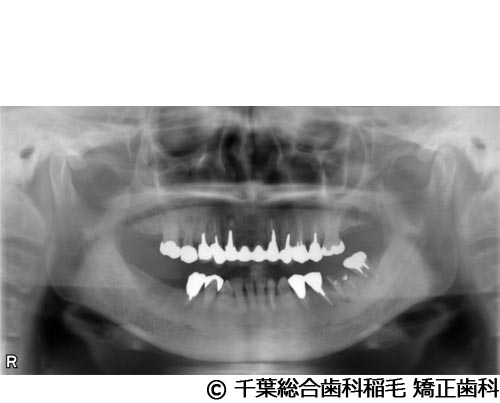

【症例1】下顎大臼歯3本インプラント埋入手術

- 治療前

- 治療後

- 治療名

- 下顎大臼歯3本インプラント埋入手術

- 費用

- 1,400,000円(税込)

- 期間

- 10ヵ月

治療内容

-

患者様の症状

左下第一大臼歯は他院で治療中でしたが、治療がなかなか進まず、他の部位にもお痛みが続いていたため、当院にご相談に来られました。

治療法

左下第一大臼歯は保存が厳しい状態だったため、抜歯となりました。

ご来院時から欠損状態だった右下第一、第二大臼歯も含め、欠損補綴についてお話させていただき、インプラントでの治療を選択されました。 -